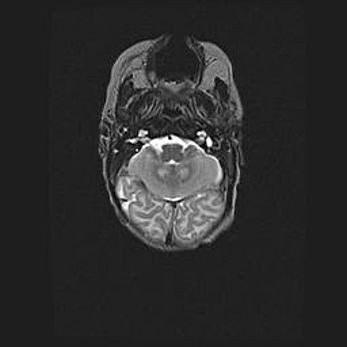

Подострая гематома правой гемисферы мозжечка.

Наружная гидроцефалия.

Возраст: 15 дней

Вес: 3100 г

Пол: женский

Окружность головы: 37 см

Срок гестации: 35-36 недель

При открытой наружной форме гидроцефалии у новорожденных расширяются и переполняются субарахноидные пространства.

Кровоизлияния в мозжечок имеют две клинико-анатомические формы: полушарные гематомы и кровоизлияния в червь.

К появлению этой патологии может привести: повреждения головного мозга, возникающие в результате асфиксии и гипоксии плода при беременности, или травмы во время родов. Редко гематома мозжечка может быть результатом первичной коагулопатии и сосудистой мальформации, диссеминированном внутрисосудистом свертывании, изоиммунной тромбоцитопении.